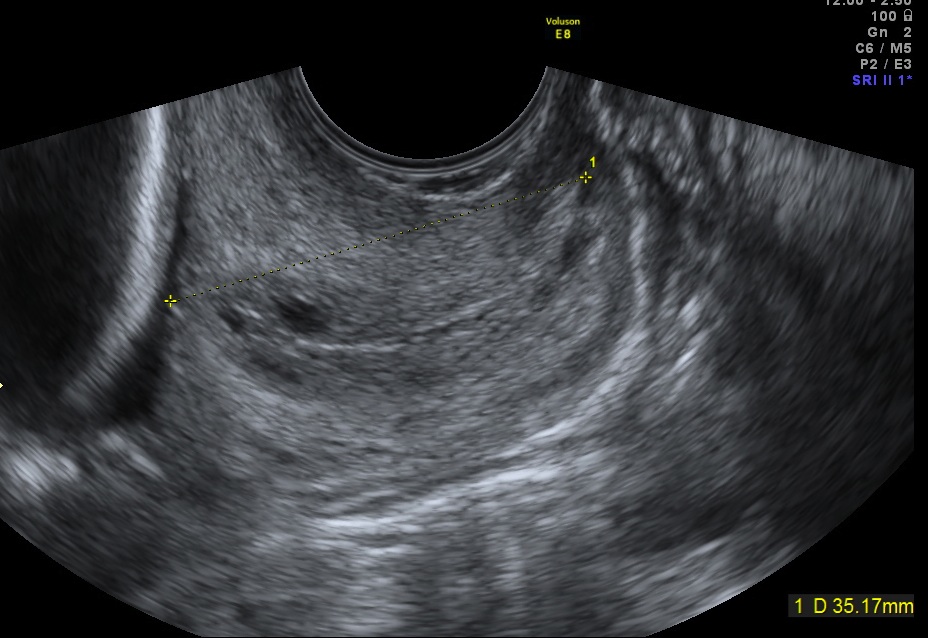

Esempio di cervice normale- La lunghezza del Esempio di una cervice raccorciata senza canale cervicale è di 35 mm funneling. La lunghezza del canale cervicale è 20 mm Esempio di cervice normale lunghezza della cervice (40 mm) ma con la placenta che ricopre l' orificio uterino interno (placenta previa centrale)